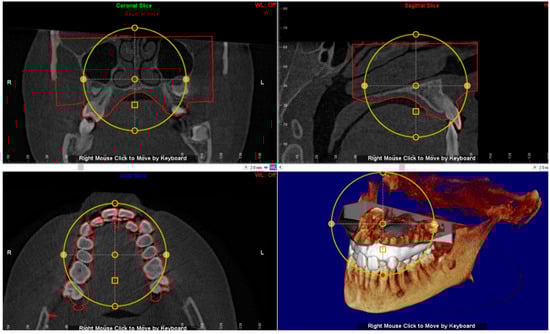

2.5. Virtual Placement of MSE (Negative Template) and Construction of the Final Lab Template

The digital model of maxillary arch is superimposed onto the CBCT DICOM file by selecting specific landmarks along the dental arch in both files (points-based registration), which allows identification of the most suitable vertical and anteroposterior placement of the MSE according to the following goals: bicortical insertion of the miniscrews, close proximity of the lower base of the MSE to the palatal mucosa and central placement of the screw using the nasal septum as visual reference (Figure 4). All these parameters were evaluated in sagittal, coronal, and axial views, and the position of the negative template of MSE was adjusted according to these parameters (Figure 5).

Figure 4.

Superimposition of the digital model of maxillary arch onto the DICOM file for identification of the most suitable vertical and anteroposterior placement of the MSE.

Figure 5.

The position of the negative template of MSE is determined in sagittal, coronal and axial views. See the design of the expander with the four miniscrews that are engaged in the cortical bone of the palate and nasal floor.

3.2. Digital Workflow for Planning MSE Device

The patient underwent a CBCT examination using the iCAT CBCT Unit (Imaging Sciences International, Hartfield, PA, USA) with the following parameters: 0.3 voxel, 8.9 s, small FOV (8 × 5 cm) at 100 kV and 20 mA. The distance between two slices was 0.3 mm, which provided accuracy in anatomic registration. The intra-oral scan was performed by using Trios 3 and exported in an .stl file using the Orthosystem software (3Shape A/S, Copenaghen, Denmark). Both the DICOM and 3D maxillary model files were imported to Dolphin 3D software (version 11.8.06.15 premium; Dolphin Imaging, Chatsworth, CA, USA) for registration and superimposition.

A negative template of MSE with four miniscrews was created using TINKERCAD software (Version 4.10, AUTODESK, San Rafael, CA, USA), according to the procedure above mentioned (Figure 3a–c). The negative MSE template was imported into Dolphin 3D software to be virtually placed in the palate. In this regard, the position of the negative MSE template was adjusted in order to reach bicorticalism of all the four miniscrews, the close proximity of the lower base of the MSE to the palatal mucosa, central placement of the screw using the nasal septum as a visual reference, the parallelism between miniscrews and nasal septum (Figure 4and Figure 5).